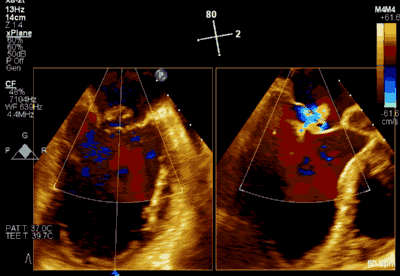

▲ 术前超声检查显示重度二尖瓣反流

▲ 术后超声检查显示轻度二尖瓣反流

患者为66岁老年男性,4个月余前因“急性心肌梗死合并二尖瓣后叶腱索断裂”出现心源性休克,在IABP支持下仍反复发作左心心力衰竭,经过急诊血运重建联合优化药物治疗后症状好转,但术后多次发作严重左心心力衰竭,超声心动图评估二尖瓣反流急性增加至极重度,左房、左室显著扩大。此次主诉“反复胸闷、气促4月余”入院。诊断:心脏瓣膜病 二尖瓣脱垂伴重度关闭不全 二尖瓣后叶腱索断裂 心功能IV级(NYHA分级) 。术前经胸超声心动图示:全心扩大,二尖瓣后叶脱垂、腱索断裂合并重度关闭不全(DMR 4+)。心脏测值:LA 45mm LVD 55mm EF% 61% PASP 82mmHg。经食管超声心动图示:二尖瓣环左右径33mm,反流束缩流颈宽度为5.5mm,EROA 0.67cm2(PISA),舒张期二尖瓣口平均跨瓣压差5mmHg。

患者全麻以后,在经食道超声心动图和X射线引导下,经股静脉入路,将MitraClip瓣膜夹顺利送至二尖瓣前后叶交界中心处,成功捕捉二尖瓣前叶A2和后叶P2,经超声心动图反复确认瓣叶夹持牢固后,测定有效夹持长度10.4mm,评估反流量降至轻度,释放瓣膜夹,超声心动图评估瓣膜夹位置和功能良好,测定左房压降至26/12mmHg,再次评估反流量仍为轻度,手术顺利完成。